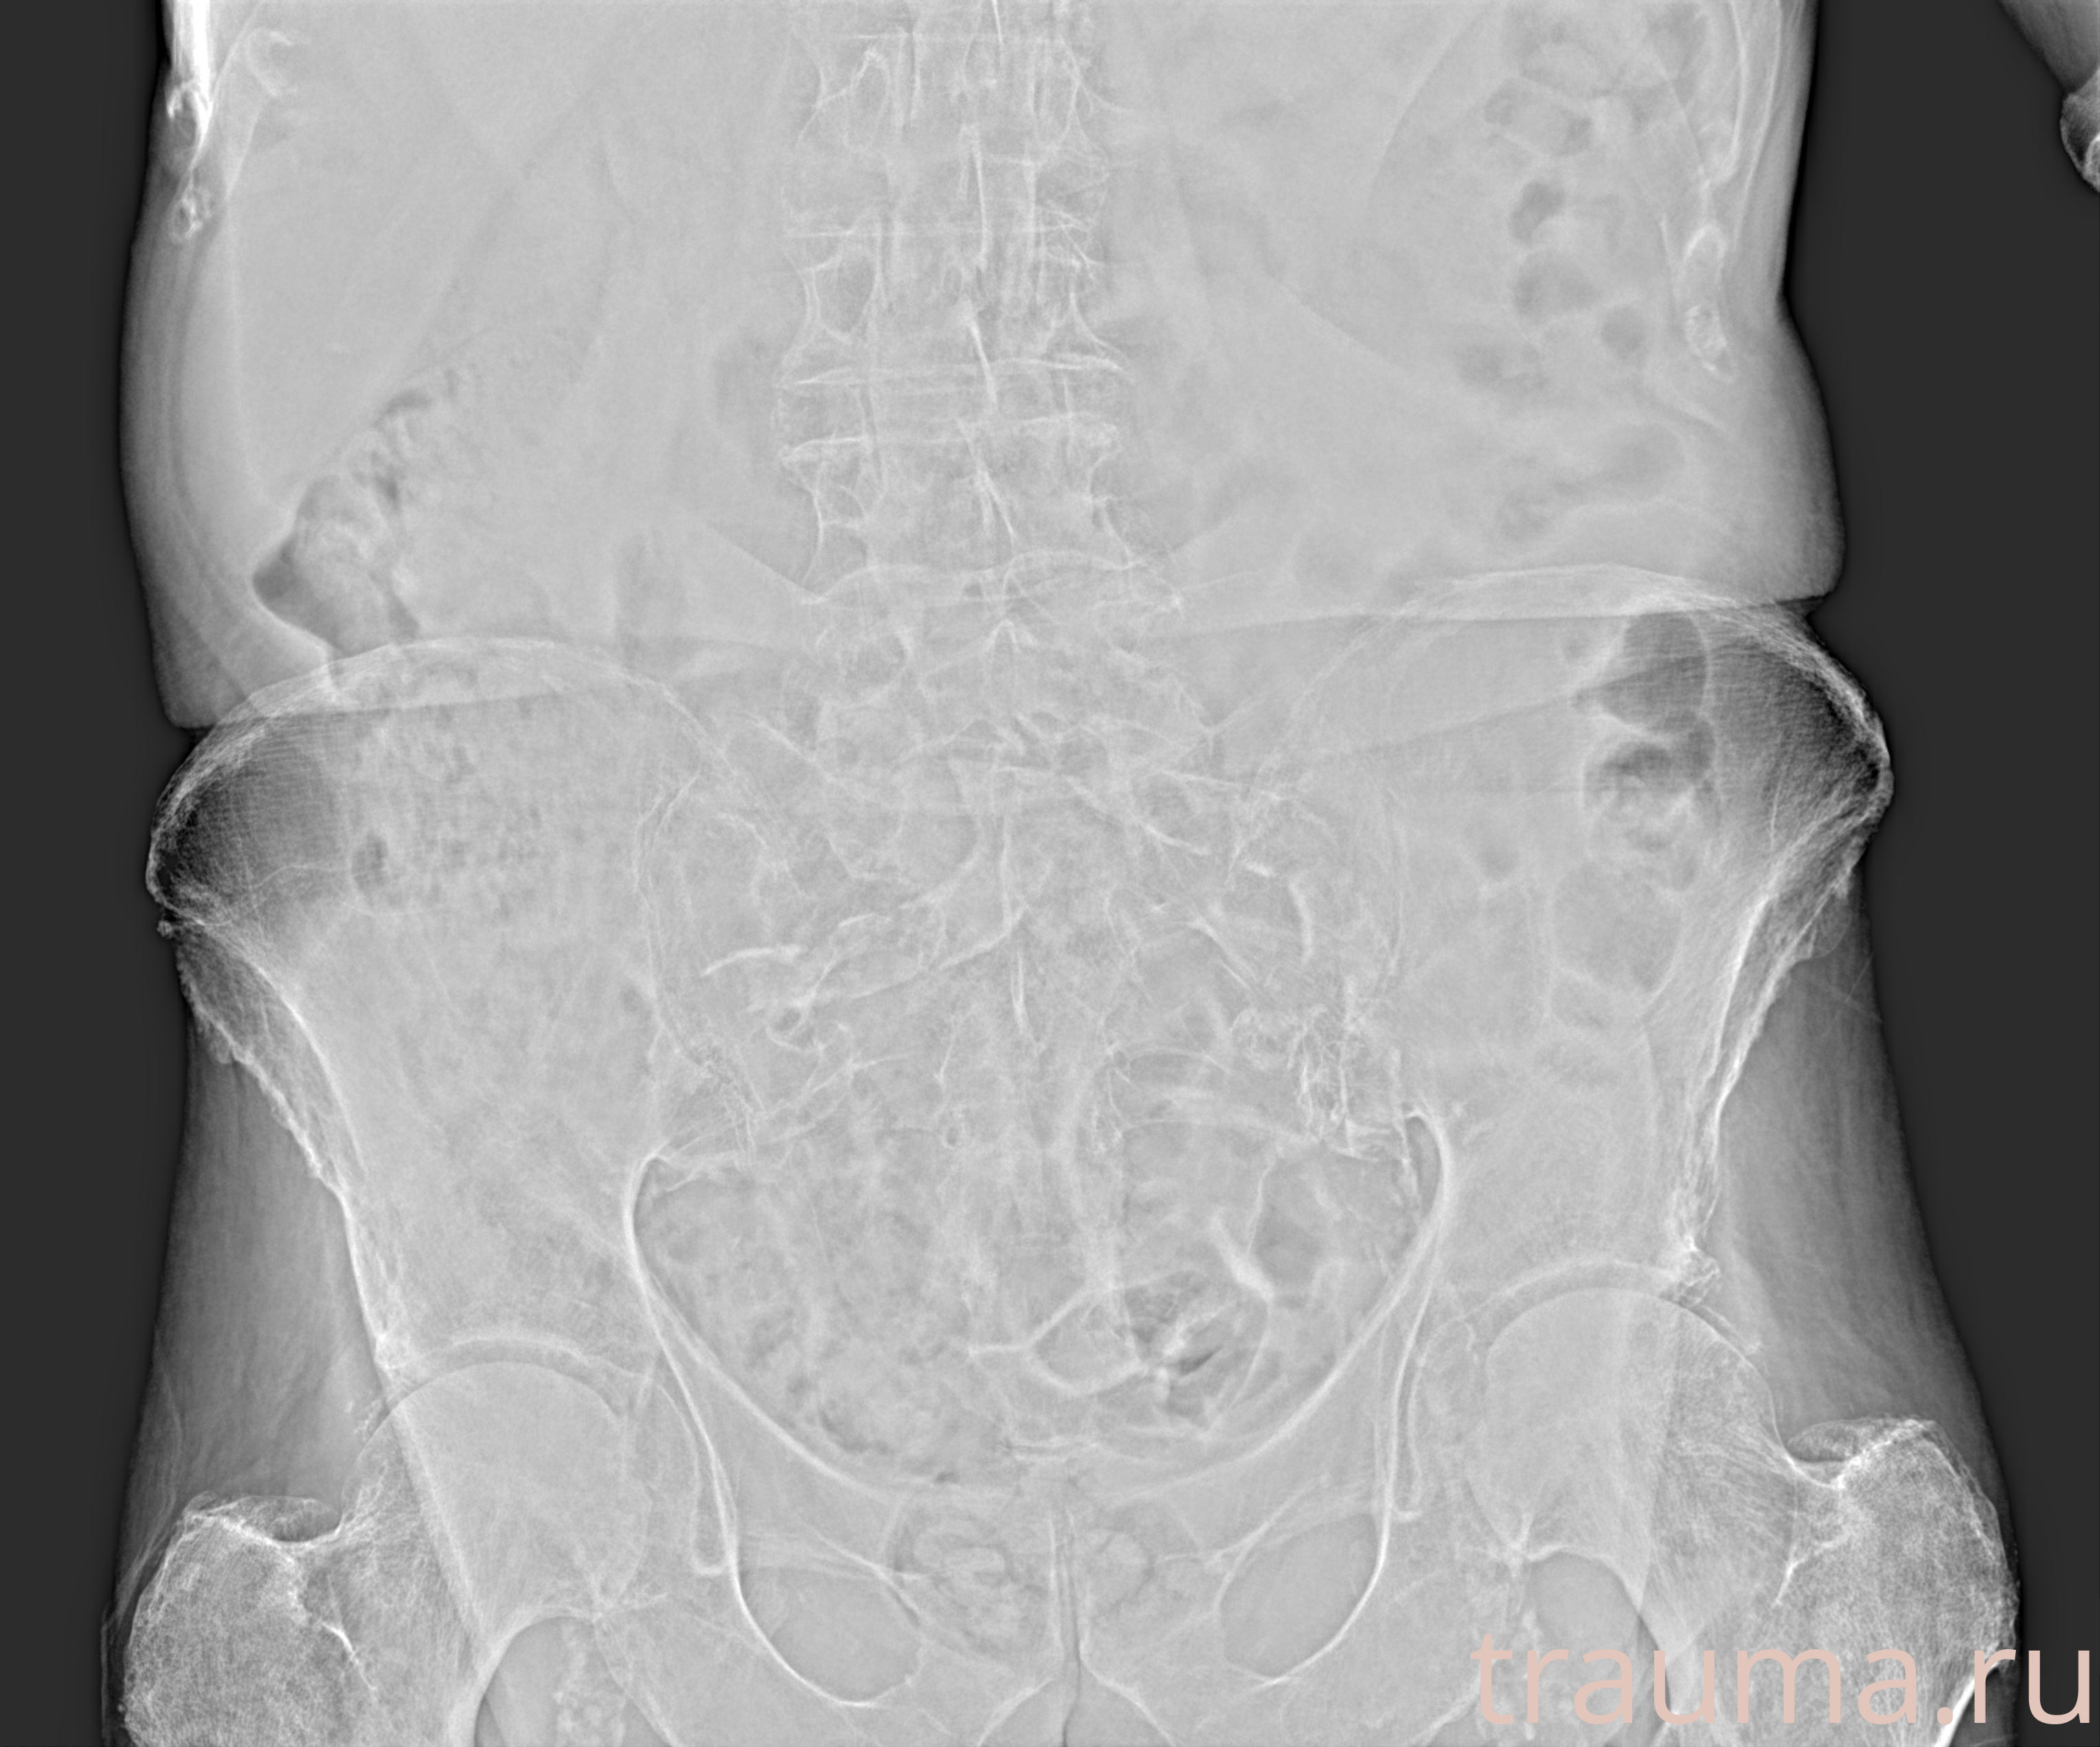

Рентген на дому: по вашему адресу приезжает врач-рентгенолог, травматолог-ортопед с мобильным рентгеновским аппаратом, проводит диагностику травмы или заболевания, делает необходимые рентгенограммы, дает рекомендации по дальнейшему лечению. Получить качественные снимки в домашних условиях возможно благодаря уникальной методике, разработанной МосРентген Центром для института  Склифосовского